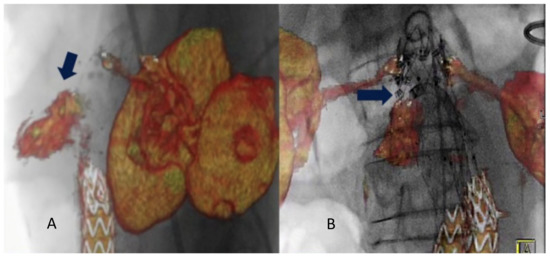

- Tinelli, G.; De Nigris, F.; Flore, R.; Santoliquido, A.; Tshomba, Y. Endoanchors under 3D image fusion for a type IA endoleak after EVAR. Clin. Case Rep. 2019, 7, 529–532. [Google Scholar] [CrossRef]